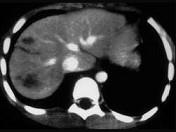

问题 下列图像最佳诊断是 ( )

选项 A、小肠破裂 B、胰腺损伤 C、结肠破裂 D、肝破裂 E、脾破裂

答案 D